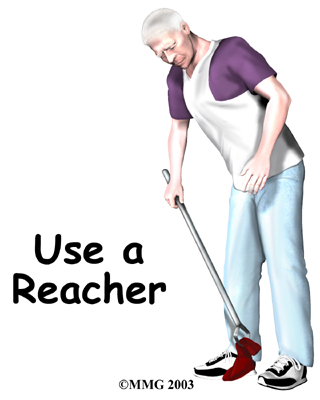

- Don't bend over past ninety degrees at the waist. Your hip may go past ninety degrees if you bend over at the waist to tie your shoes or pick up items off the floor.

Instead, use a reacher to put on your shoes and socks or to pick up items from the floor.

Reacher

To avoid excessive bending and lifting, arrange your shelves and cupboards with frequently used items at waist to shoulder height. For lighter items on lower shelves, be sure to have your grabber handy to keep from bending over too far at the hip.